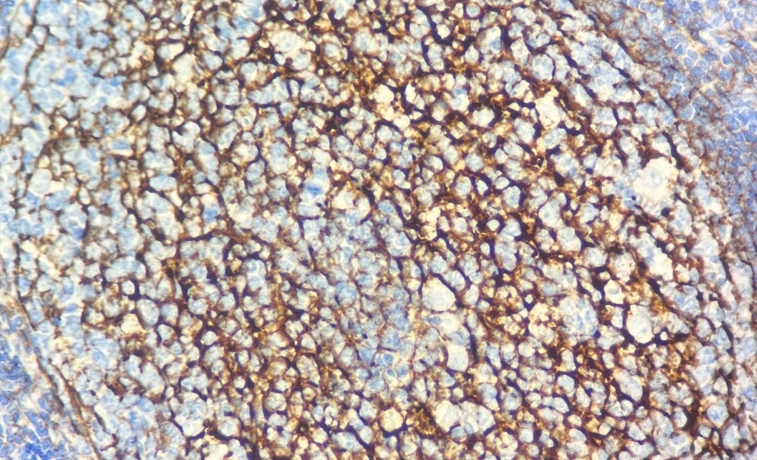

CD35(补体受体1/CR1)是一种介导补体调理化免疫复合物处理与清除的关键受体,又称C3b/C4b受体或免疫黏附受体。在生理状态下,红细胞表面CD35分子数量随细胞老化逐渐减少;而在系统性红斑狼疮(SLE)、HIV感染、部分溶血性贫血等免疫复合物相关疾病中,其表达水平显著降低。CD35抗体作为成熟B细胞标志物,可特异性标记滤泡树突状网状细胞及其来源的肿瘤(如滤泡树突细胞肉瘤)。该抗原表达于红细胞、B细胞、T细胞亚群、单核细胞以及嗜酸性粒细胞和中性粒细胞表面,在免疫微环境调控及抗原提呈过程中发挥重要作用。

阳性部位:

细胞膜